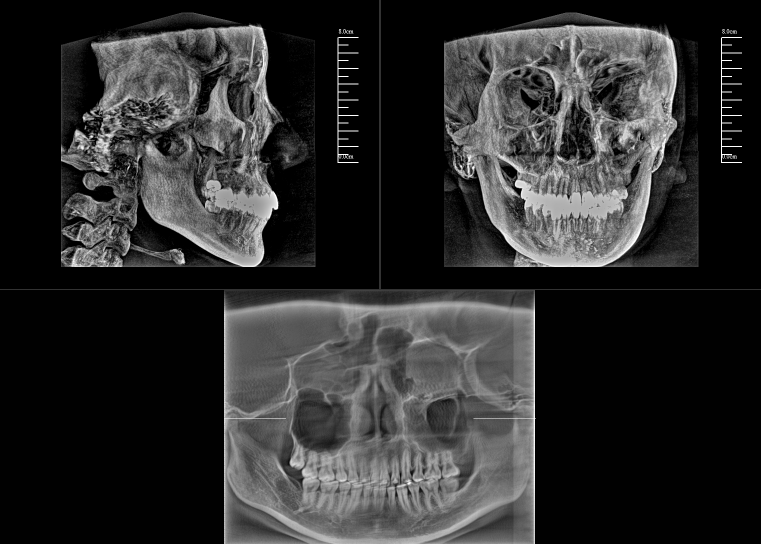

CBCT,全称“锥束计算机断层扫描(Cone-Beam Computed Tomography,CBCT)”,由球管和平板探测器组成。与全科CT的闭环圆孔设计不同,数字化口腔CBCT采用开放式结构以保持其灵活性。

对于口腔内科疾病,牙片和全景片已具有较高诊断效果;但对于牙体牙髓病,2D成像较容易发生影像重叠的情况,无法进一步明确根管和其他周围组织的三维信息,容易出现漏诊或误诊根裂的情况。这就需要三维断层成像,即数字化口腔CBCT。

数字化口腔CBCT是从三维的角度,即矢状位、冠状位和横断位来显示病变组织和正常组织结构,有效的避免了2D图像固有的缺陷,如正常组织器官的影像重叠,投射角度变化所致的影像扭曲、变形等,大大提高了诊断能力。

数字化口腔CBCT能在十几秒时间内完成患者口腔扫描,进而生成高精度的三维影像,彻底解决了牙片机、全景机等传统口腔X射线设备影像重叠、畸变的问题。可以360°全方位立体观测牙床的骨质密度、牙槽骨本身的高度、宽度等数据,不仅能重建整个颅面区的结构,对颌面骨质结构进行测量,而且还能重建精细的解剖细节。